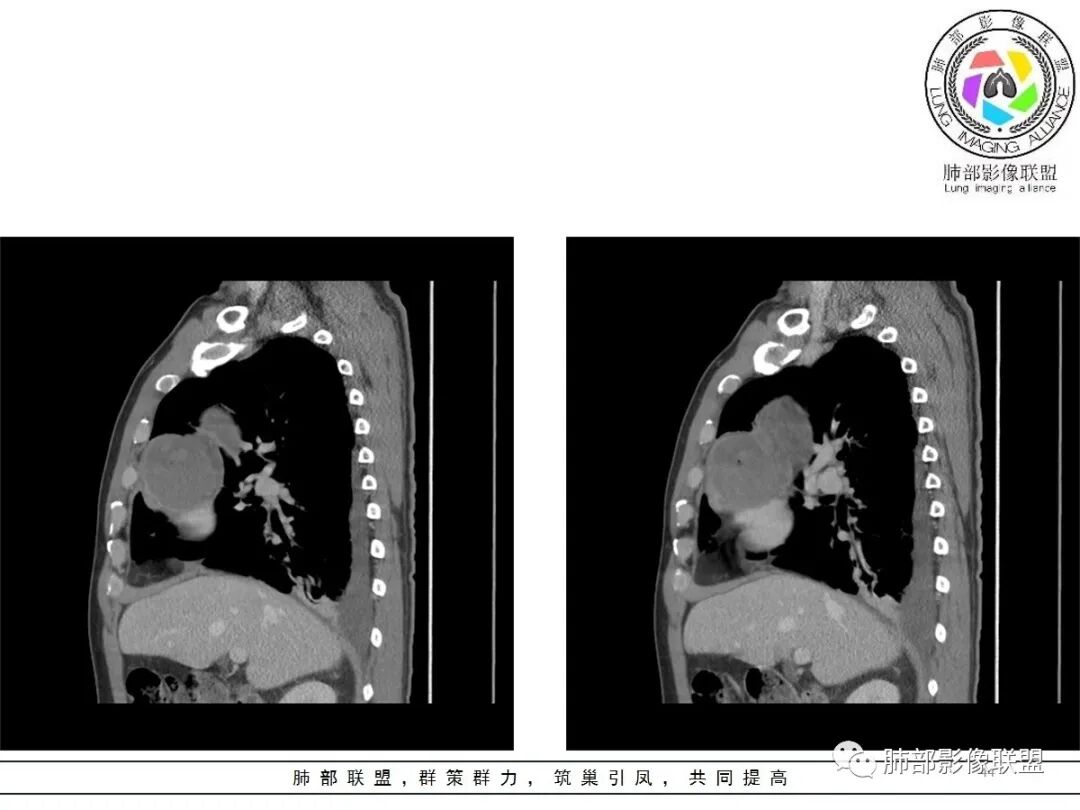

小赵:这个是3月15日的视频

小赵:第二个是3月19日的视频

周围脂肪间隙密度增高,内部小点状很低密度影

右侧少量胸水

19日,4天后, 内部低密度影有,周围渗出增多,胸水增多

薄膜状强化

影像上周围病灶变化明显

常规肿瘤侵犯不支持,太快

应该是炎性病变渗出

脂肪密度明显,还有钙化、囊性病变,支持含脂质类病变破裂

周围是化学性炎症或出血所致

后期强化,可能与炎症有关

可能:1、肿瘤或瘤样病变破裂出血或内部物质外溢所致2、炎性病变所致

对比一下:

肿瘤样病变破裂所致纵隔炎应该没错

南边:肿瘤或肿瘤样病变破裂所致纵隔炎,这是大方向

2.胸膜掀起,右侧内乳动脉略增粗,定位右前上纵隔内占位。

3.右上纵隔囊实性占位,边界清楚。中央见点状脂肪密度影,边缘见一点状钙化影,增强不均匀环形强化。

4.四天内病灶变化快,块影增大且不规则,包膜似不完整,边界不清,上份可见浸润或渗出,与周围心脏大血管及心包等间隙不清。胸水增多。

5.未见明显淋巴结增大

第一次的检查符合胸腺瘤影像学改变,短期内的形态学改变及突然出现的边界模糊或浸润等,符合出血或炎症。